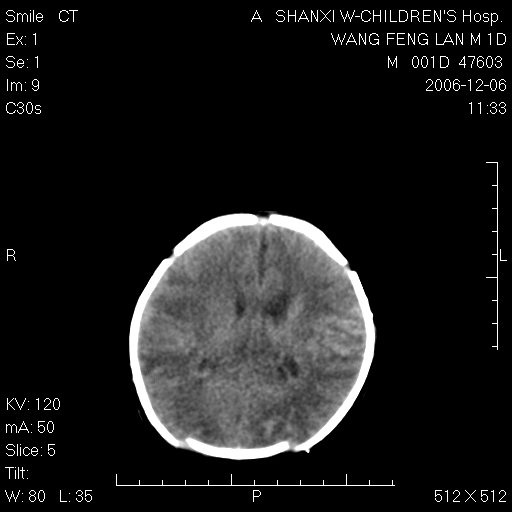

以下是引用husiling在2006-12-6 18:14:00的发言:[br]1\\hie[br]2\\蛛血.

以下是引用zjzjr在2006-12-6 19:29:00的发言:[br]支持新生儿缺血缺氧性脑病伴少量蛛网膜下腔出血.

以下是引用卜一在2006-12-6 21:38:00的发言:[br][br] 支持:新生儿缺血缺氧性脑病伴少量蛛网膜下腔出血 [br]